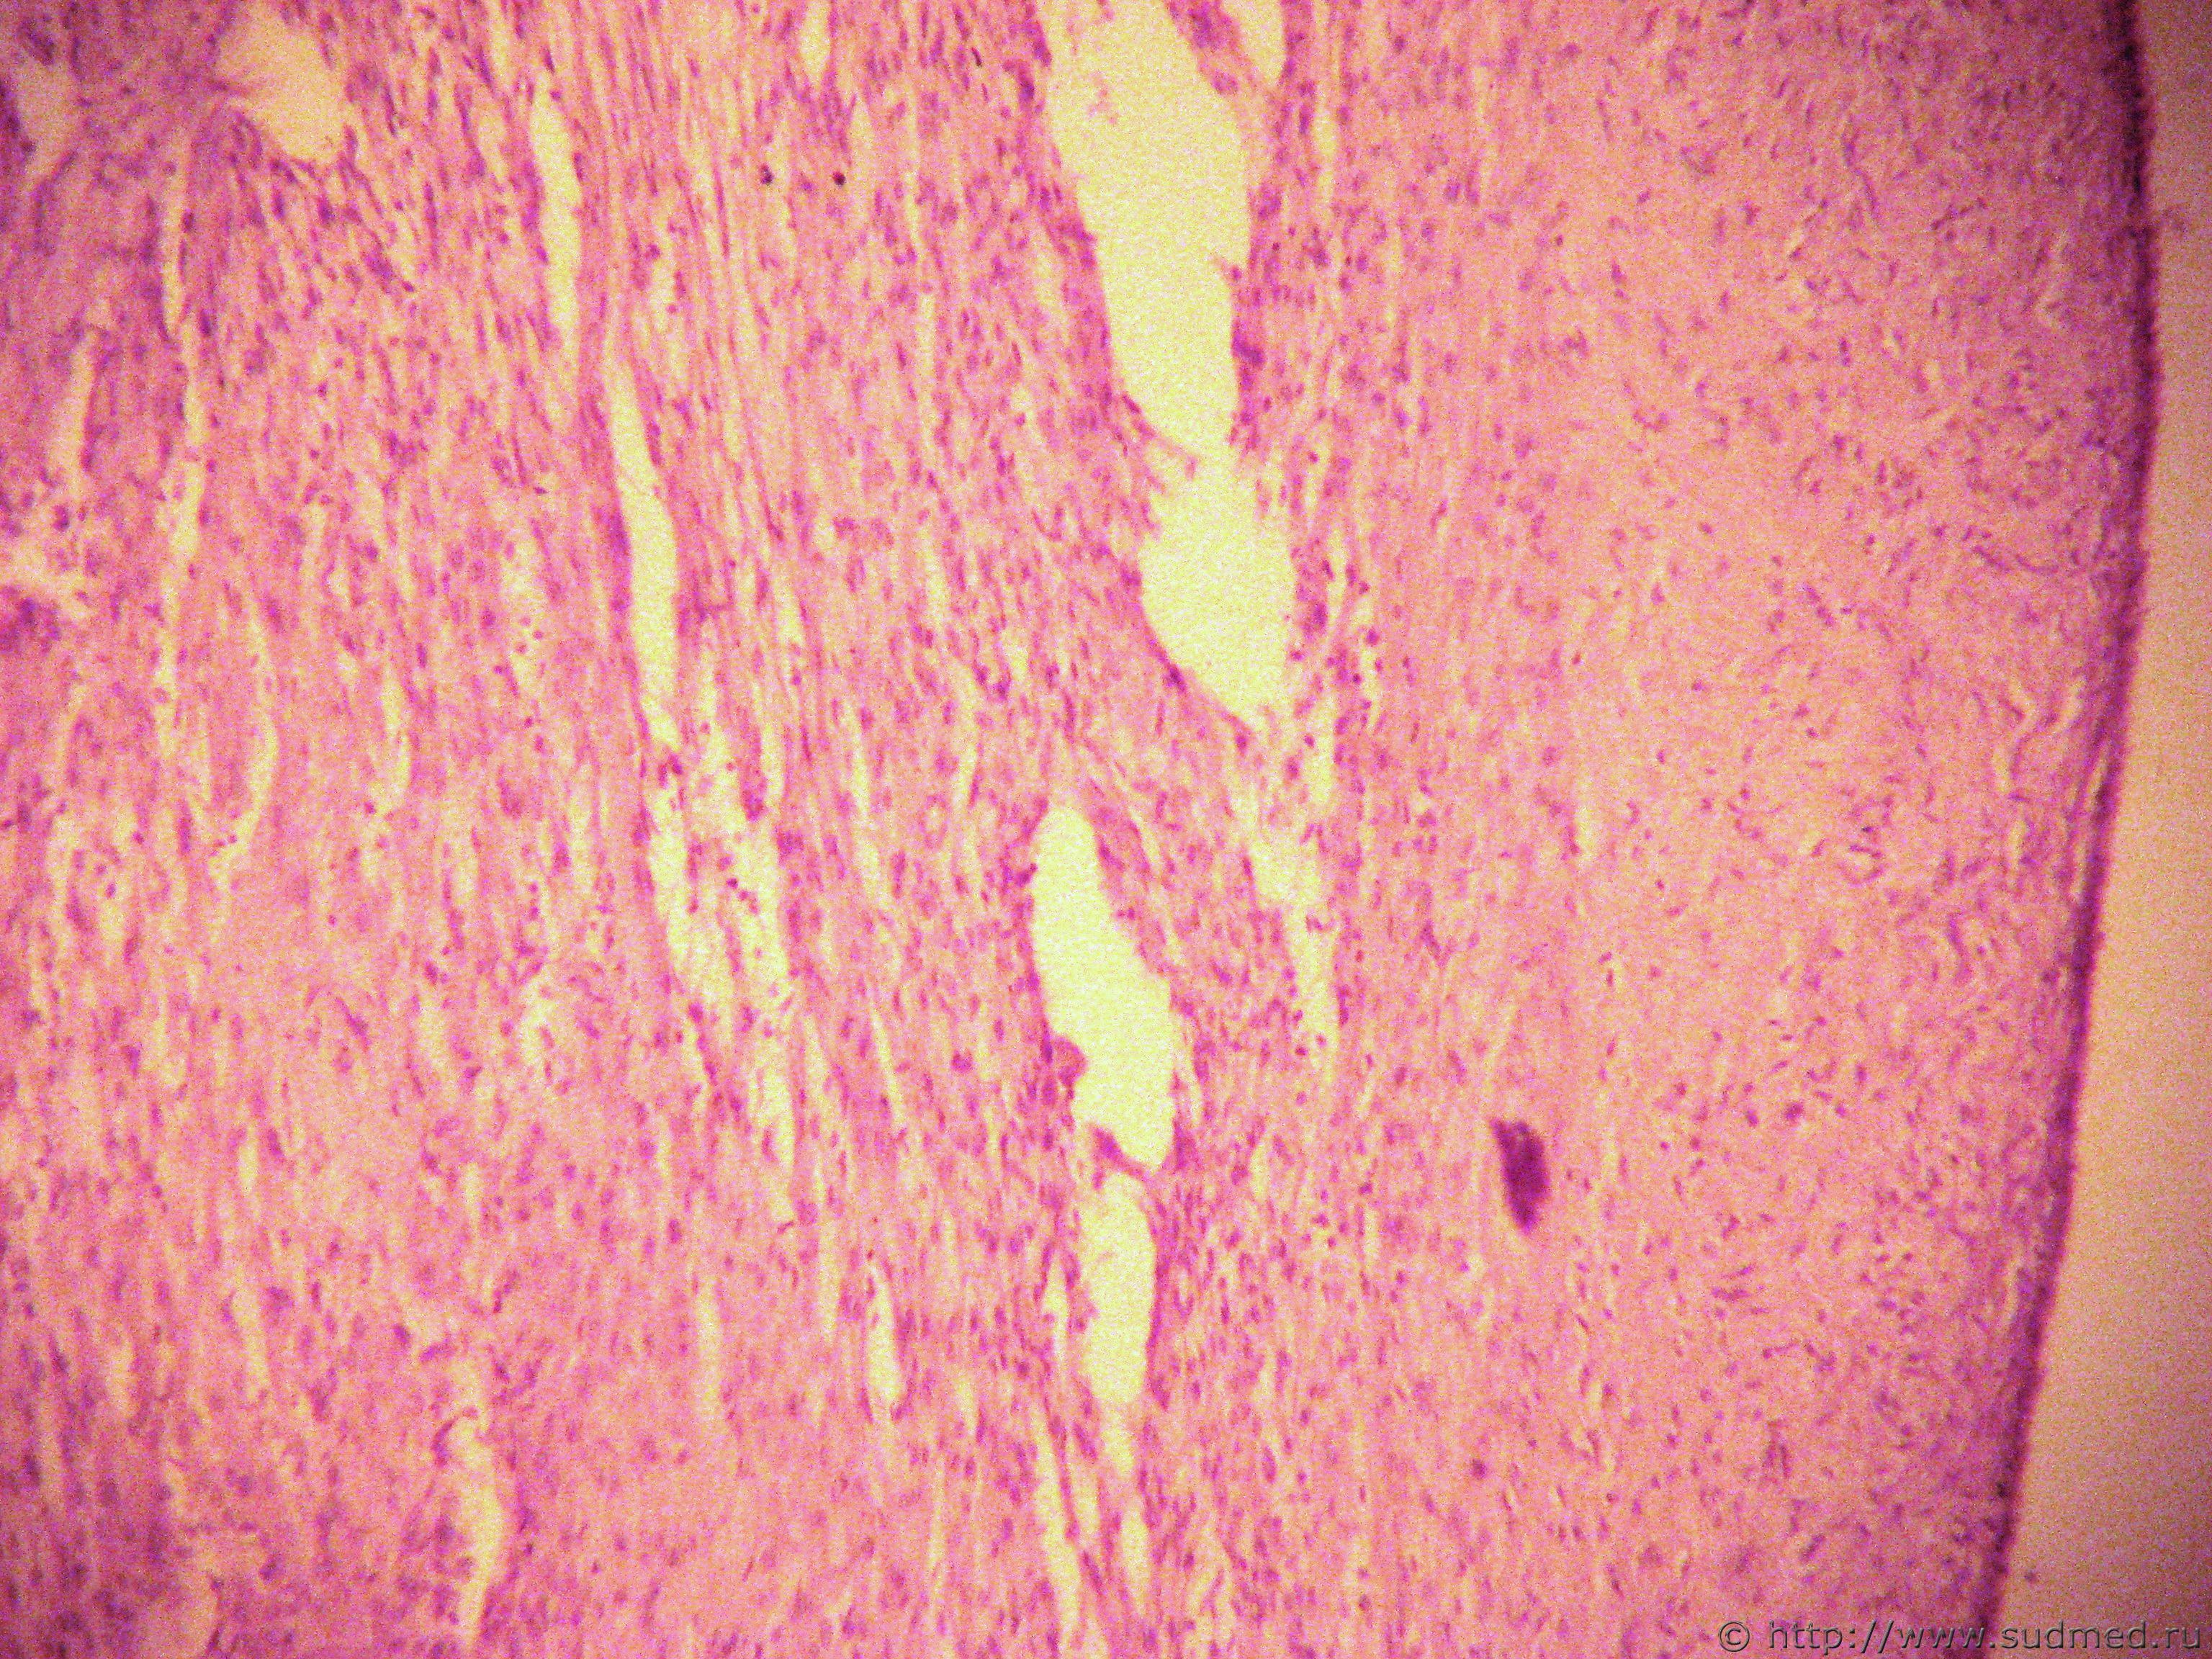

Фото 1. ХОБЛ. спирали слизи в бронхах. пневмосклероз

Фото 2, 3 - сердце. Фото 4 - лёгкие. Фиброэластоз. Ребёнок 1.5 мес. Поступал в инфекц.больницу с подозрением на 2-стороннюю пневмонию, дыхание ослаблено. На R-снимке лёгкие в виде тонких полос. Сердце выполняет весь объём плевральных полостей. Случай не мой. Вскрытие в ПАО.